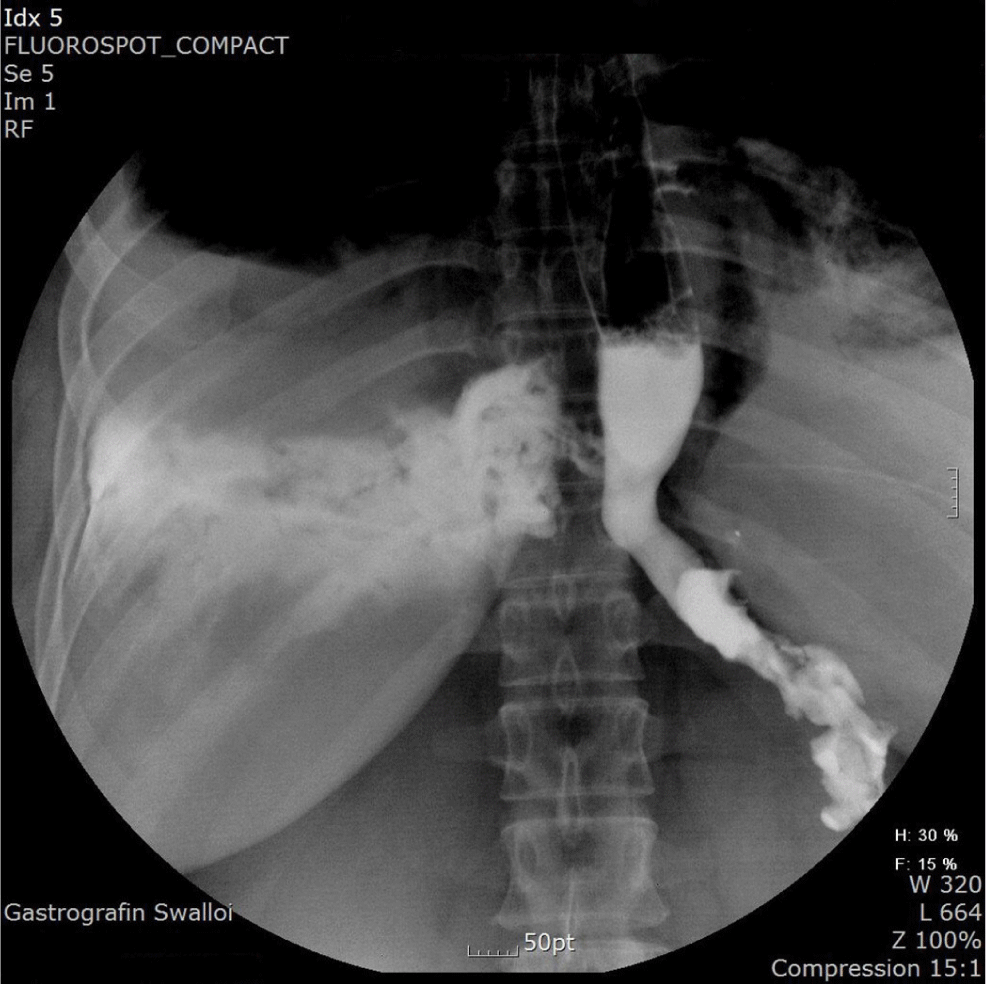

Esophageal perforation following gastric calibration tube insertion during laparoscopic sleeve gastrectomy

J Biomed Transl Res 2025;26(3):79-83.

https://doi.org/10.12729/jbtr.2025.26.3.79